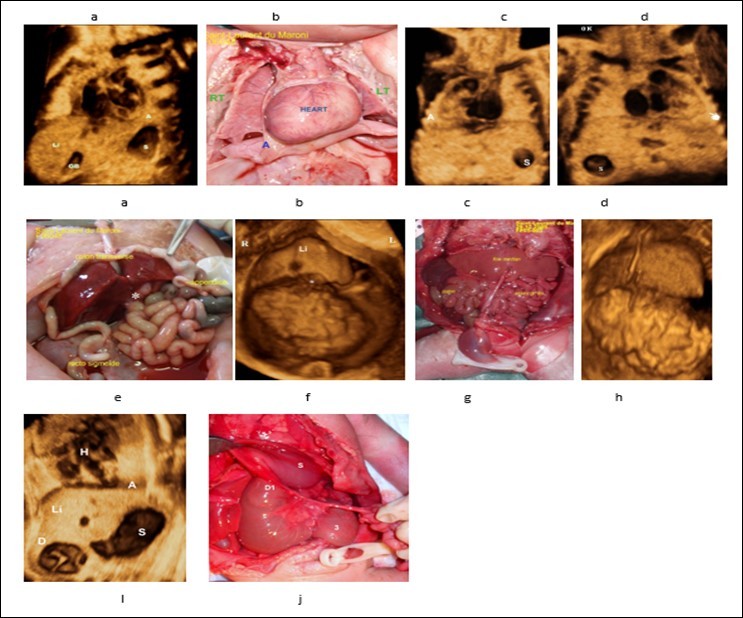

Figure 1.a)Case control, 3D volume of normal situs solitus (28 weeks’ Gestation). The heart and stomach are on the left; the gallbladder is on the right, liver is predominantly on the right side. b,c) Dextrocardia , echo-anatomic correlation. D) Stomach are on the right side , Apex of the heart is on the left.e,f) Liver in the median position (echo-anatomic correlation), appendix and gall bladder ((white asterisk) are on the left side, rectosigmoid is on the right side.g)Nonrotation , the entire small bowel localizing to the right abdomen and colon localizing to the left abdomen. h- Liver in the median position (echo-anatomic correlation with g). i) Grey scale frontal view, showing the characteristic “double-bubble” appearance of the stomach and duodenum, note that the apex of the heart is toward the stomach i.e. left side.j) (echo-anatomic correlation with i) D1 first part of duodenum , S stomach , *** Ladd's bands (cause of obstruction).A). Apes of the heart S: Staomach R: Right L: Lefi Li: Liver . H: Hand denting apex of the heart GB: Gall Bladder.

One patient had dextrocardia in which the diagnosis was evoked by by Doppler imaging following localization of the apex of the heart and axis of the left hepatic vein on opposite sides, both left hepatic vein (LHV) and the apex of the heart are in the same side and point to the same direction i.e. downwards, the cardiac apex points to an opposite direction with respect to the spine i.e. away from the spine. (Figure 2d). In levocardia the cardiac apex is oriented away from the spine, on the other hand, in dextrocardia, the cardiac apex is oriented toward the spine (Figure 2). The 4 patients had a liver in the median position , one patient had the appendix appendix and gall bladder ((white asterisk) are on the left side, rectosigmoid is on the right side.(Figure 1 a,b,c,d,f). And another patient had intestinal nonrotation, the entire small bowel localizing to the right abdomen and colon localizing to the left abdomen. (figure g,h). One patient had congenital duodenal obstruction caused by Ladd's bands (Figure 1 I,j)

One of our patients had nonrotation with the entire small bowel localizing to the right abdomen and colon localizing to the left abdomen and another patient had incomplete rotation), appendix and gall bladder ((white asterisk) are on the left side, rectosigmoid is on the right side. (Figure 1 e, f)

A mismatch between the position of the fetal stomach and cardiac apex may be one of the first signs indicating atrial isomerism. 27. 2 patients had the stomach in the right side, one of them without congenital heart disease. (Figure 1 d, Figure 3b).

In our previous work 31, we demonstrated that, in parasagittal view, both left hepatic vein (LHV) and the apex of the heart are in the same side and point to the same direction. Thus , the diagnosis of dextrocardia is achieved by Doppler imaging following localization of the apex of the heart and axis of the left hepatic vein, furthermore, in normal position (levocardia) the cardiac apex is oriented away from the spine (Figure 2 a) , on the other hand, in dextrocardia, the cardiac apex is oriented toward the spine (Figure 2 d ) , to the best of our knowledge , this the first study evoking the diagnosis of situs using these parameters (orientation of cardiac apex with regard to LHV and spine). Another example demonstrating the utility of this parasagittal view is shown in (Figure 2 e, f), the LHV is pointing in the opposite direction to the cardiac apex i.e. upwards toward the thorax, a diagnostic clue to diaphragmatic hernia, in this case e diagnosis was confirmed by fetopathological examination. In addition, Grayscale facilitated the diagnosis of situs and confirmed the diagnosis of dextrocardia and right-sided stomach and midline position of the liver (Figure 1).